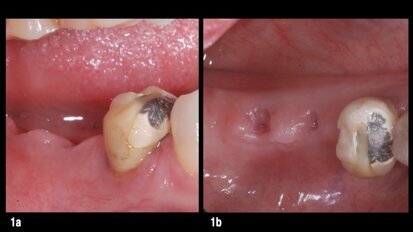

Colocación de sobredentadura sobre raíz natural del diente en paciente edéntulo

Los autores describen el procedimiento más sencillo, económico y funcional para la rehabilitación del paciente edéntulo total, por medio de la ...